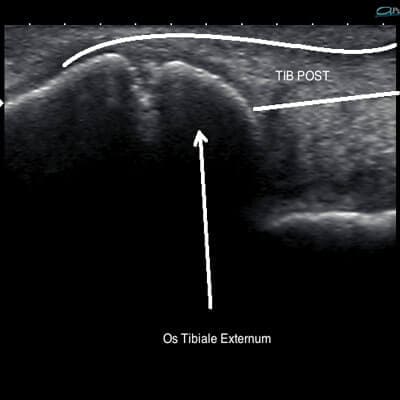

Tibialis posterior tendon

Accessory Navicular Syndrome